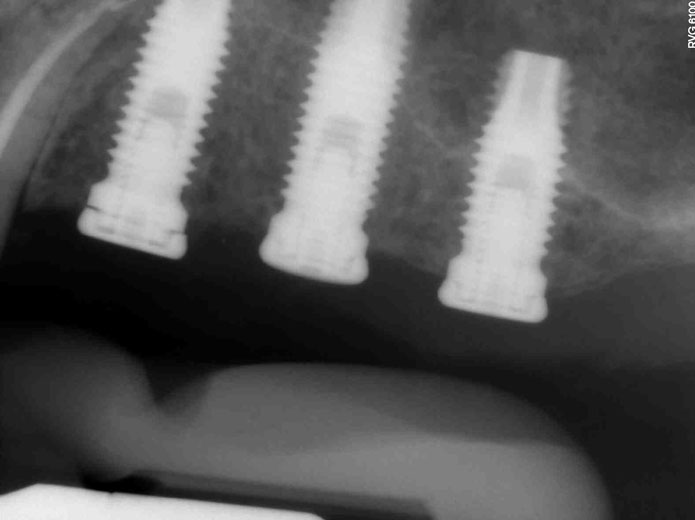

Αποκατάσταση πλήρους έλλειψης δοντιών (άνω ή/και κάτω γνάθου)

Σε περιπτώσεις που αντιμετωπίζουμε πλήρη έλλειψη δοντιών στη γνάθο:

• Στην κάτω γνάθο τοποθετούνται 4-6 εμφυτεύματα

• Στην άνω γνάθο τοποθετούνται 6-8 εμφυτεύματα

Ο αριθμός αυτός των εμφυτευμάτων εξασφαλίζει την κατασκευή μιας σταθερής προσθετικής αποκατάστασης, ικανής να αντέξει το βάρος των μασητικών δυνάμεων κατά τη σύγκλειση, χωρίς να δημιουργεί δυσανάλογες φορτίσεις στα εμφυτεύματα.